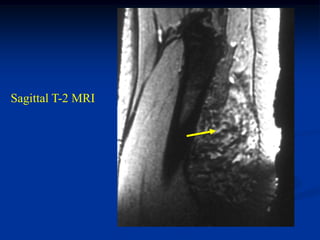

Case #286                 Sagittal T-2 MRI

tumor

43 year male with myxoid liposarcoma behind knee

Coronal T-2 MRI

Axial T-1 MRI